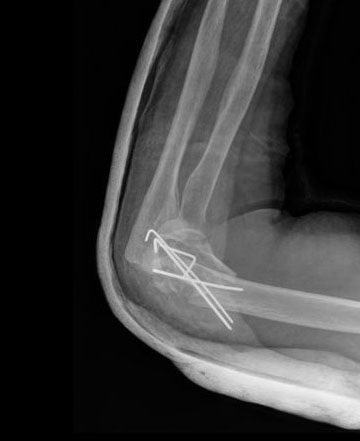

Fractura de olécranon con osteosíntesis.